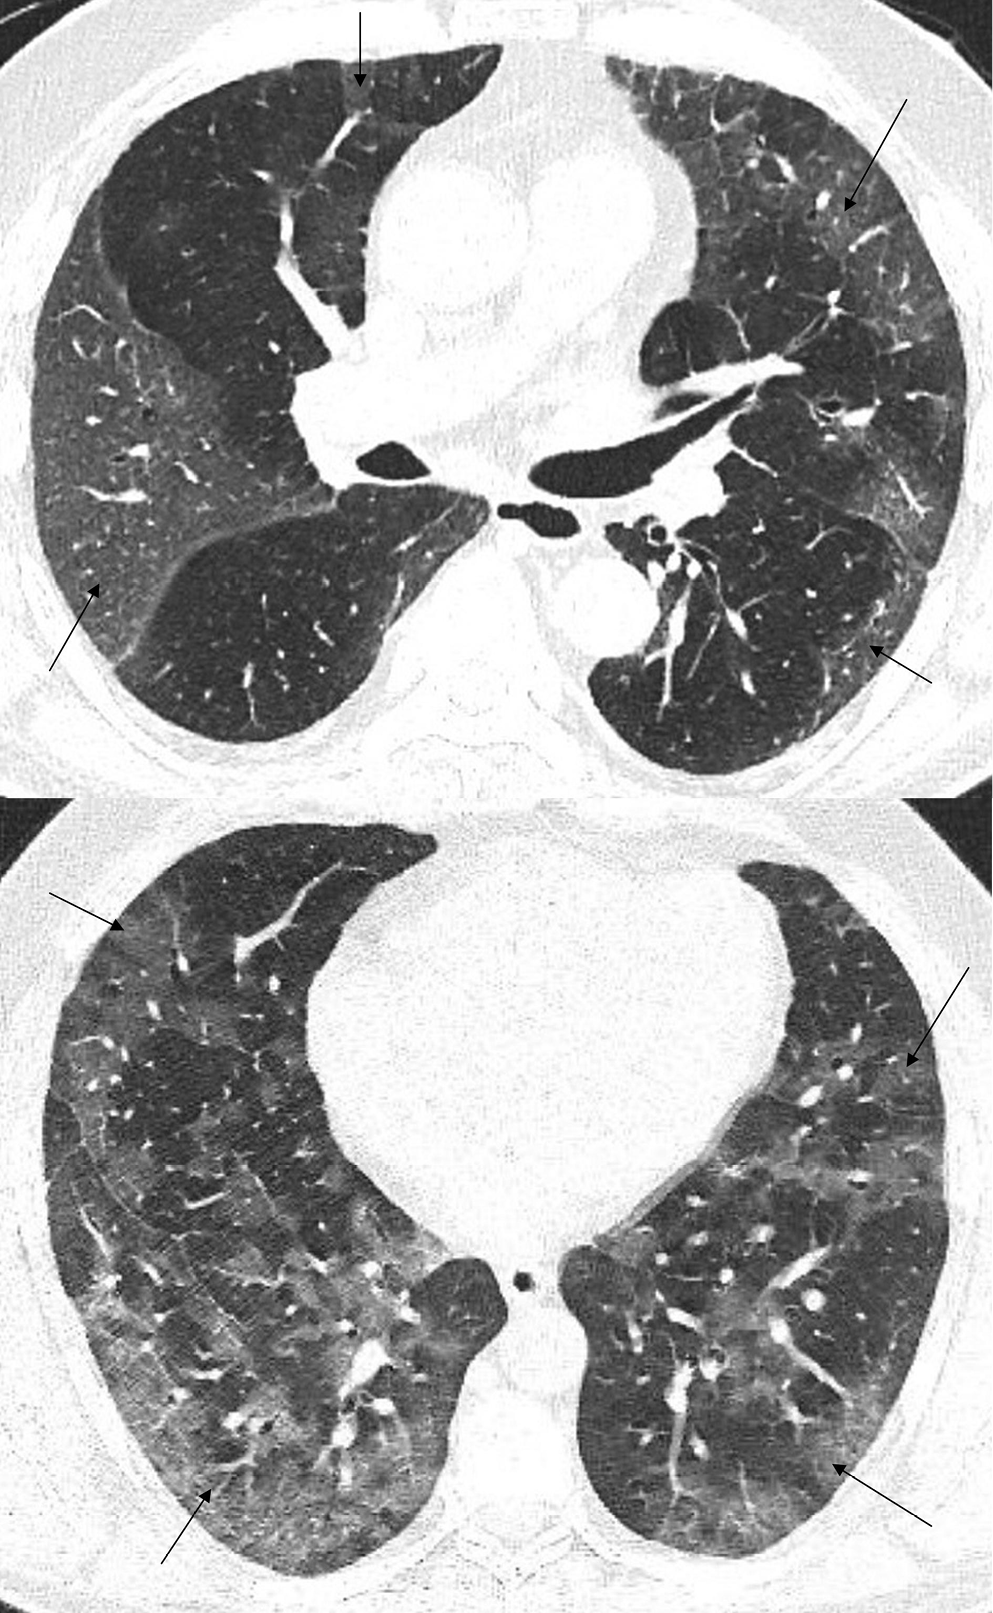

In the early stage of COVID-19, the primary CT findings observed are bilateral GGOs with a mostly peripheral and subpleural location. Ground-glass opacity is a term used to describe hazy areas with the preservation of vascular and bronchial margins which are a result of the partial filling of air spaces, intestinal thickening, or the coexistence of both (Figure 2).10 Another phenomenon is described as having ‘crazy-paving’ appearance. This is a combination of GGO and interlobular or intralobular septal thickening (Figure 3). This condition is mostly present in severe cases of COVID-19 pneumonia. Consolidations (multifocal, patchy or segmental) are another sign of COVID-19 progression (Figure 4).11 Several days after developing the first symptoms, chest CT can reveal linear consolidations and reversed halo signs in the patient’s lungs.12 Radiographic features typically include bronchovascular thickening (Figure 5).13

Recently, COVID-19 progression has been described with successive CT scans and has been correlated with the onset of symptoms. Shi et al. monitored a patient for 3 weeks and performed 4 CT scans.14 The 1st CT scan, obtained 9 days after the onset of symptoms, revealed multifocal bilateral GGOs. After 15 days of disease evolution, a mixed pattern of GGOs and consolidations was observed. The signs of healing were seen after 19 days. The last CT scan was performed on day 31 and no abnormalities were found.14

A retrospective study of 121 symptomatic patients infected with SARS-CoV-2 was performed by Bernheim et al.15 The main aim of their research was to assess the correlation between the onset of symptoms and common findings on the initial CT scan. The time between the occurrence of the first symptoms and subsequent CT scans was divided into 3 periods: early (0–2 days); intermediate (3–5 days); and late (6–12 days). Bilateral lung evolvement, which is considered typical in COVID-19 pneumonia, was observed in 28% of early-stage patients, 76% of intermediate-stage ones and 88% of late-stage patients. Crazy-paving appearance and the reversed halo effect were absent in the early group, but were mostly present in the late-stage group. It was found that 56% of the early patients showed the lack of lung capacities during the radiological examination despite the presence of clinical symptoms. The study results exhibit imaging patterns, essential not only for understanding the pathophysiology or natural history of COVID-19, but also for the prediction of its progression and potential complications.15

Based on similar research, 4 stages of CT imaging have been established. The 1st stage is named the early or initial stage and lasts up to 4 days. A CT scan performed during this period may not reveal any pathologies or may only indicate the presence of GGOs. It is crucial to remember that up to half of patients may have a normal CT scan 2 days after the symptoms occur. The next phase is the progressive stage (5–8 days) – several GGOs arise and the crazy-paving pattern becomes visible. Between 9 and 13 days, consolidations appear. This phase is called the peak stage. After 14 days, absorption begins and fibrous stripes may occur (Figure 6). After at least 1 month, and if no other complications arise, the patient’s lungs are able to return to a condition similar to that before COVID-19.16